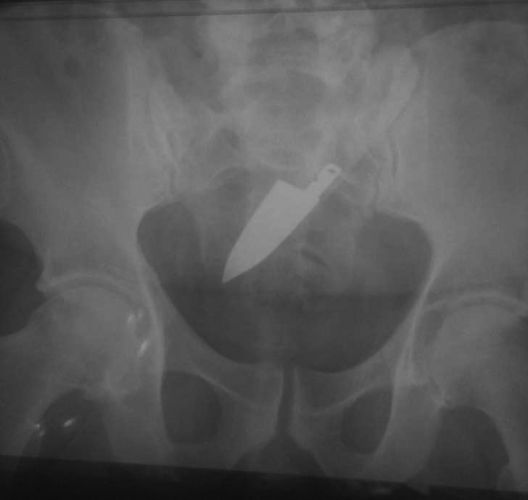

© Reprodução

Faca